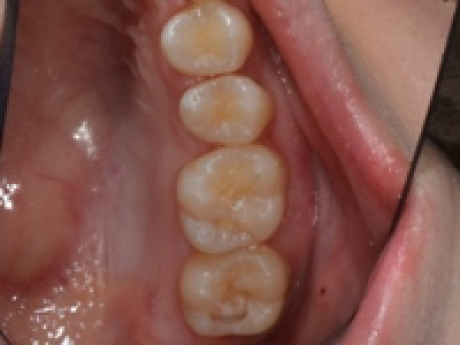

case2